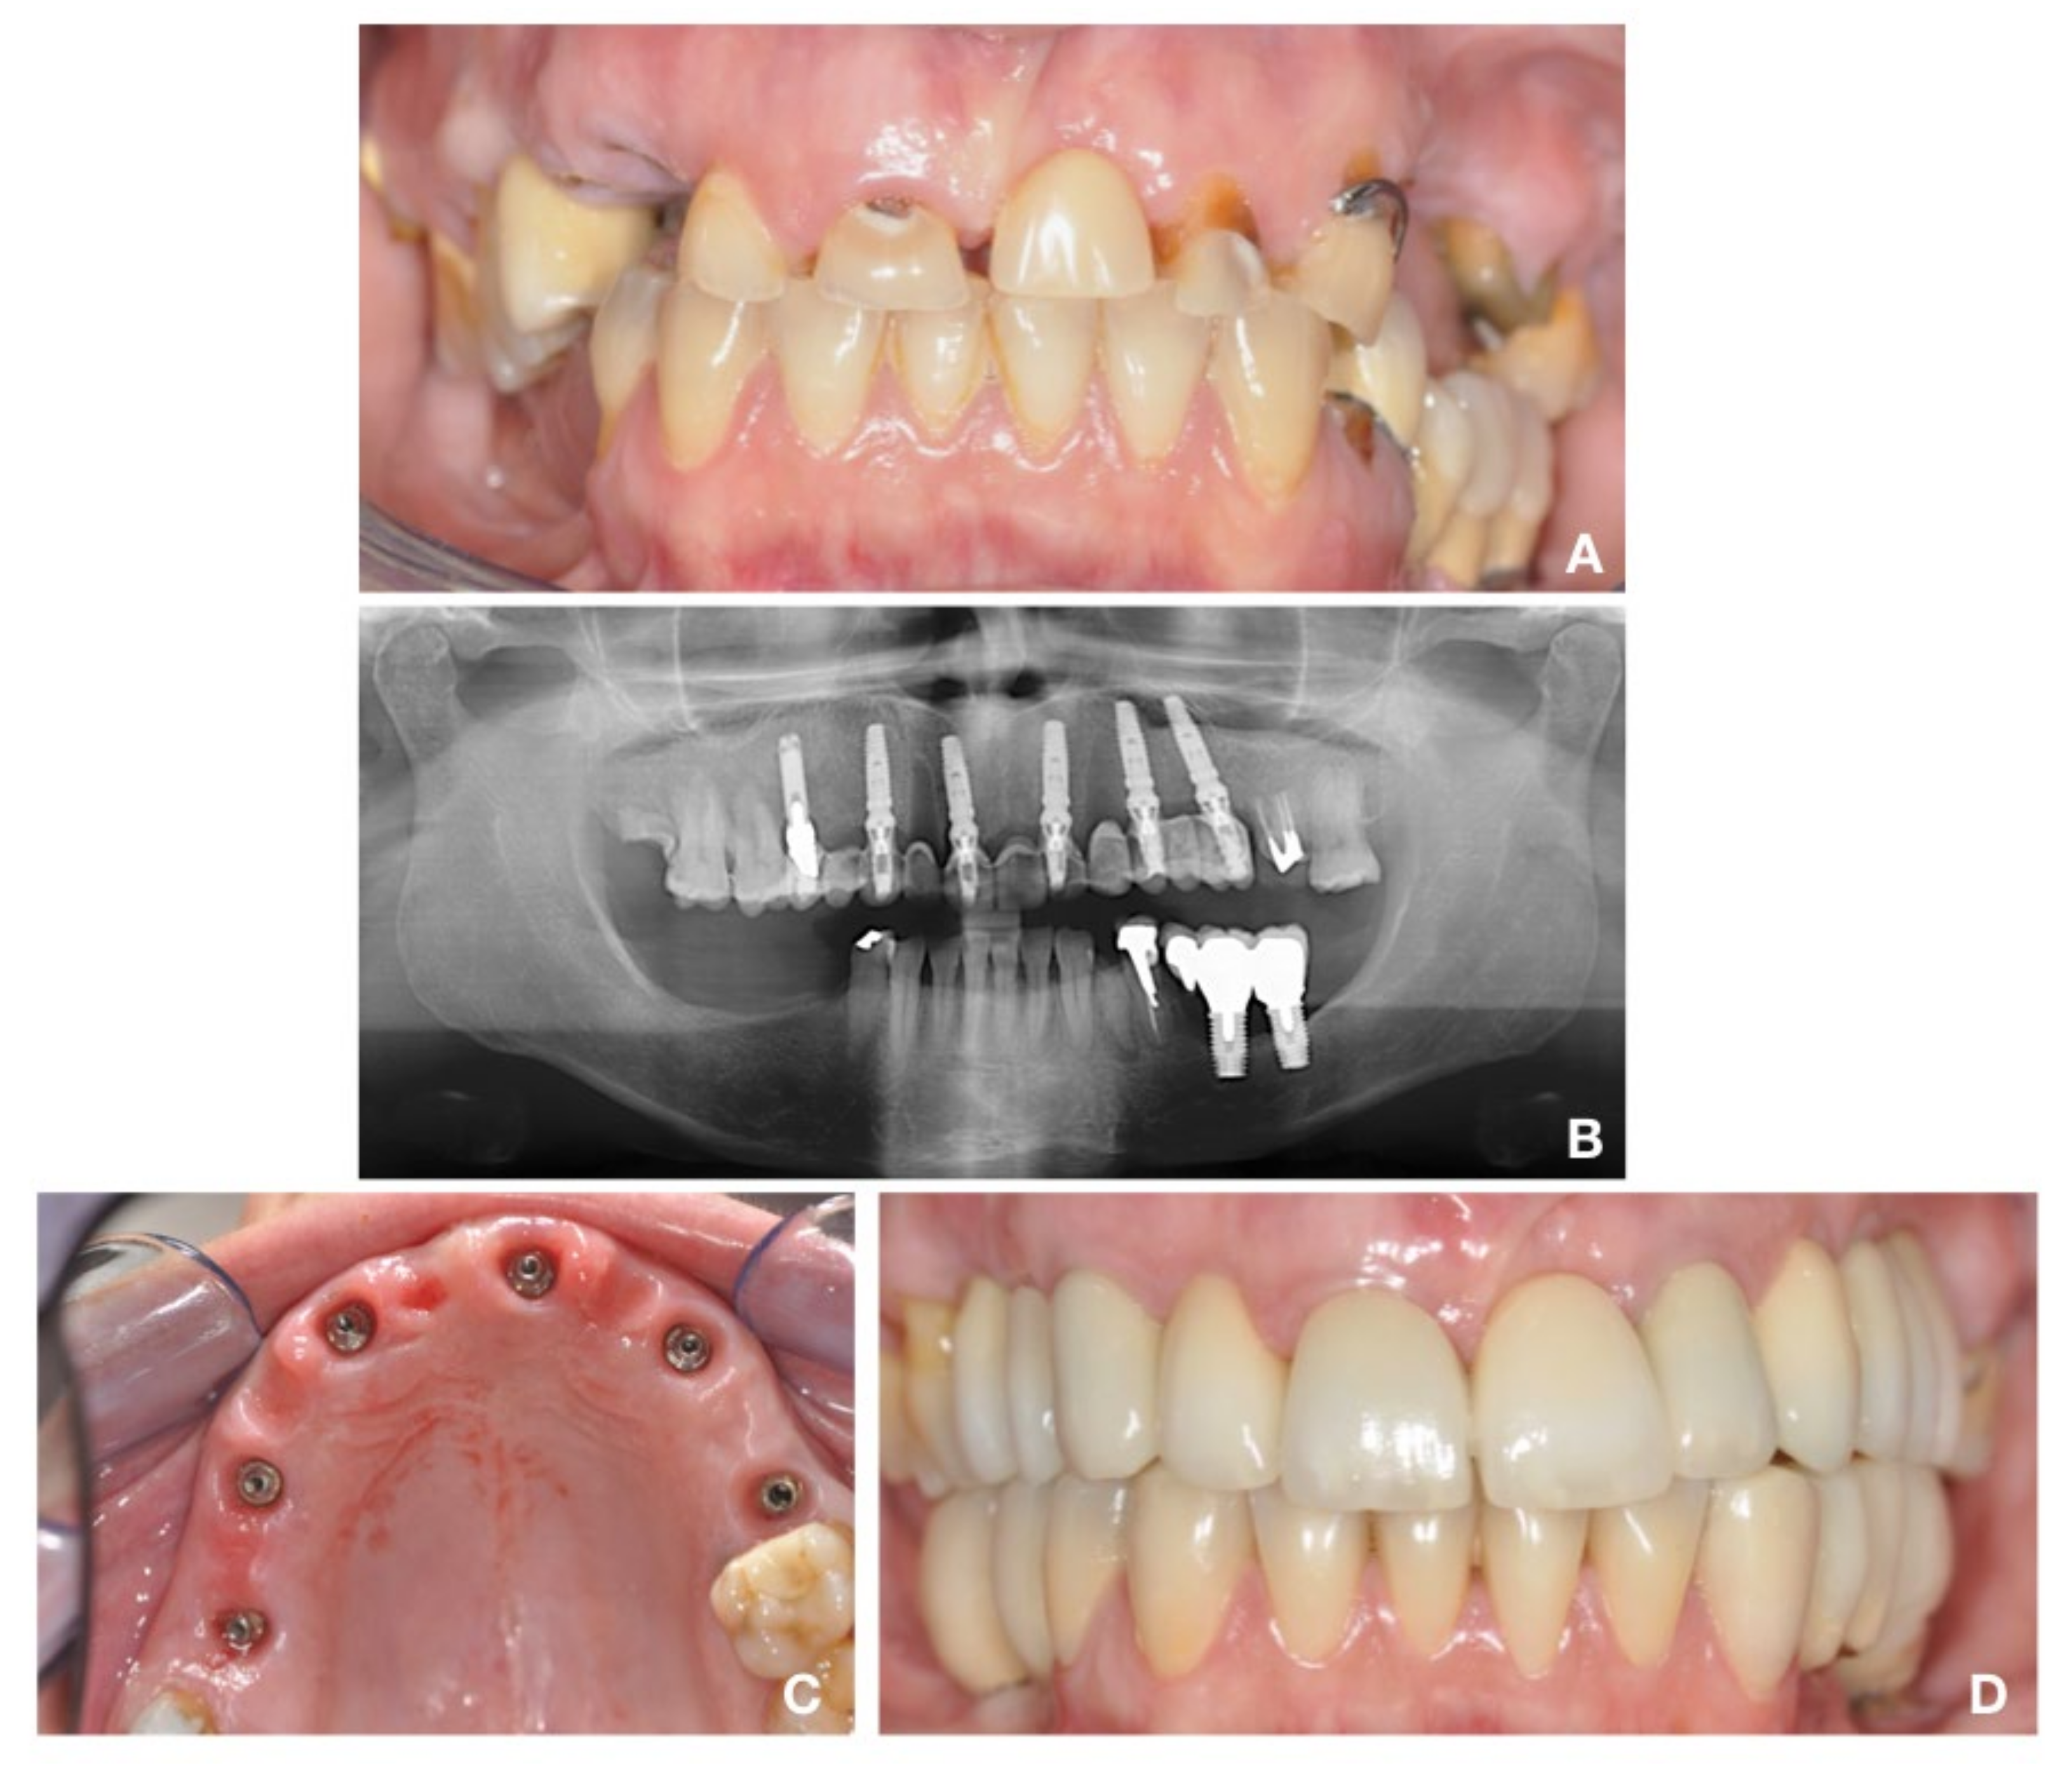

2.3. Surgical Protocol: “Biological Oriented Immediate Loading” (B.O.I.L)

2.4. Prosthetic Protocol